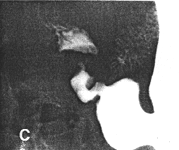

Case 28.3 L.M., 50 year old female. Radiographic examination showed pronounced, constant contraction of the pyloric sphincteric cylinder; occasionally a minor degree of relaxation occurred, but cyclical contraction and relaxation was absent and most of the time the appearance remained as illustrated (Fig. 28.3). Prominent circular and irregular mucosal folds which appreared to be immobile, were present in the contracted cylinder. A concave indentation was seen in the base of the duodenal bulb. Endoscopy revealed a number of mucosal erosions as well as an appearance of severe "antral" gastritis. This was still present at a second endoscopy 8 months later, indicating chronicity.

![]() |

| Fig. 28.3. Case L.M. Constant contraction of sphincteric cylinder (arrows), with prominent irregular, static mucosal folds |